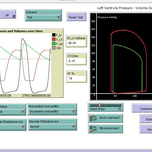

| Anesthesia & Intensive Care / Cardiovascular System | Victor Iapascurta | 1 | false | |

| Anesthesia & Intensive Care / Respiratory System | Victor Iapascurta | 4 | false | |

| Dynamical Systems & Chaos Models | Victor Iapascurta | 11 | false | |

| Medicine / Anesthesia & Intensive Care | Victor Iapascurta | 2 | false | |